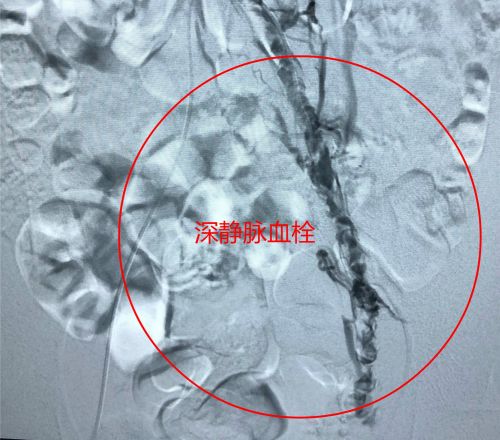

术前,下肢深静脉血栓形成。

术后血管造影显示,深静脉通畅。